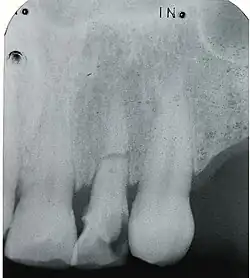

Messaufnahme – während der Wurzelbehandlung eines frakturierten Frontzahnes (11)